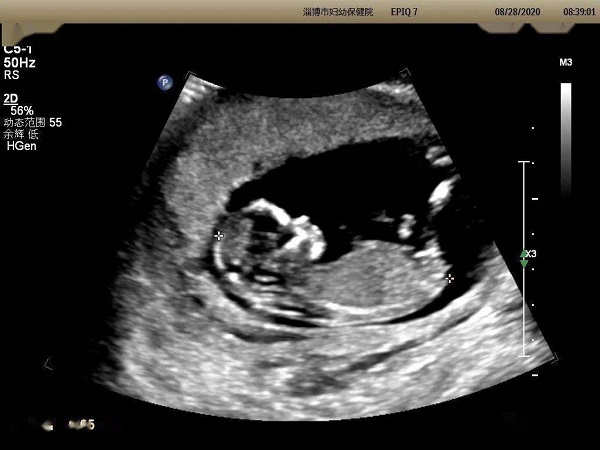

网上流传通过怀孕13周的Nt单子可以看出胎儿性别,但是很多孕妈妈都不知道具体应该怎么看。下面为大家整理了13周已生男宝的nt单子,大家可以对照看一下。

其实在怀孕13周的时候,胎儿的生殖器官已经基本发育完全,通过B超检查是能够看到的,但是由于国家禁止,因此医生是不会告知父母胎儿性别的。据此,网上就有不少人传通过Nt单子上的图片也是可以看到胎儿的生殖器官特点的。

胎儿两腿间有亮点就说明是男宝宝

认为如果nt单子上胎儿两腿之间有白色的亮点,那就是男孩子的睾丸,所以出现白点的nt单子大概率就是男宝宝。但是如果看到胎儿两腿之间是三条白线的话,其实就是女孩子***的形状,怀女宝宝的概率会更大一些。并且有已经生育男宝宝的姐妹验证,nt单子上确实有白点存在。

但其实,nt单子的图像还会受到宝宝姿势和医生检查位置的影响,因此单纯通过nt单子有无亮点和白线来判断生男生女还是不可靠的。建议大家不要太关注宝宝的性别,应该多关注孩子的健康状况。